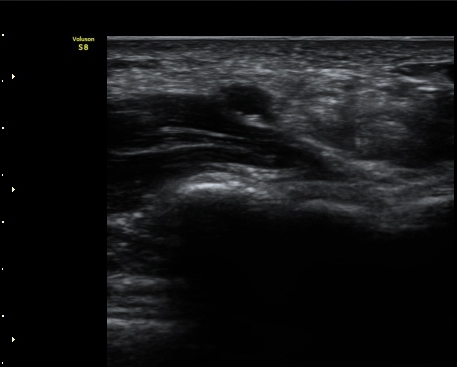

¼Õ¸ñ(lunate ±âÁØ)°ú ¼ö±Ù°ü ±ÙÀ§ºÎ(scaphoid ±âÁØ) Á¤Á߽Űæ Ⱦ´Ü¸é°Ë»ç¿¡¼­ Á¤»óÀûÀÎ

¸ð¾çÀ¸·Î °üÂûµÈ´Ù(±×¸² 1, 2).